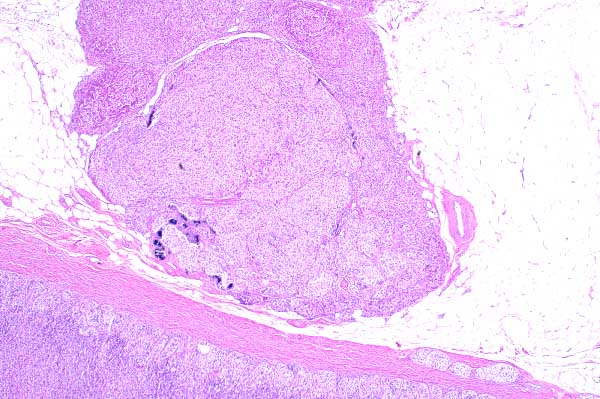

| 2x   |   Hematoxylin and Eosin | ||||

There is an extracapsular and an intracapsular nodule of adrenal cortical cells.